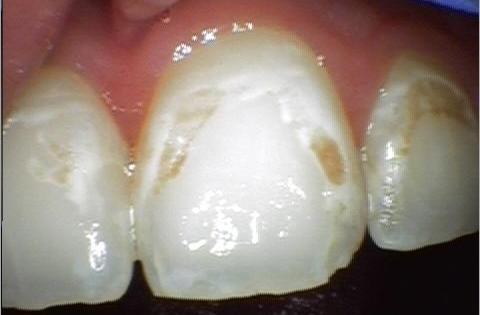

These bacteria feed on the traces of the food you eat that are left in your mouth. As they metabolize these food particles, they produce acid. Over time, this acid can damage the structure of the teeth. Diligently brushing and flossing helps remove plaque, a sticky mixture of saliva, food particles, and bacteria that clings to your teeth.

If plaque is allowed to remain in place for too long, the acid erodes parts of your tooth, creating a hole. This is a cavity. If left untreated, the cavity will grow, allowing bacteria to penetrate further into the tooth and cause pain.

Dr. Terveen will remove the decay in and around your tooth and then restore it using a composite resin filling.

Even with diligent brushing and flossing alongside dental check-ups, cavities can still happen. In the past, the only options for fillings were porcelain, gold, or silver amalgam materials. The problem with metal amalgams is their tendency to darken over time, as well as requiring removal of healthy tooth structure to hold the filling.

Our office provides a variety of different filling materials to suit the individual needs of each patient; however, most of these fillings are tooth-colored composite. Composite has many benefits, such as blending naturally with the tooth, bonding to the remaining structure, and acting relatively inert in your mouth.